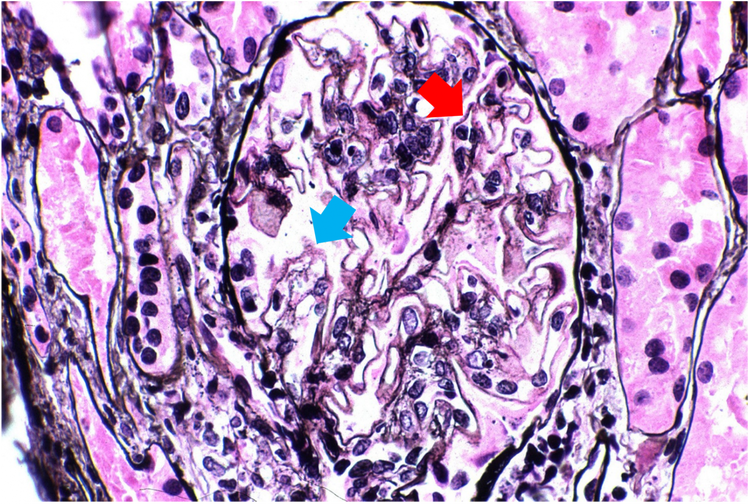

それに対して図2で、LNクラス5の進行期患者のサンプルは、糸球体基底膜に沿って拡散した穴(青い矢印)や小さなスパイク(赤い矢印)を示しています。3